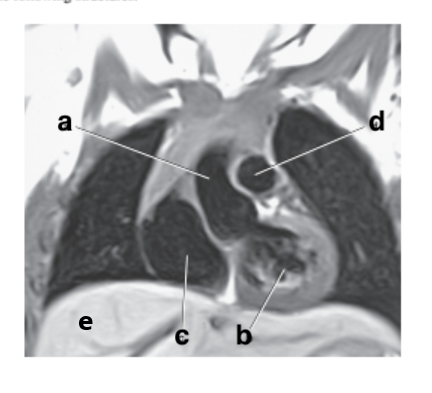

Left atrium

What is letter b ?

Left ventricle

Aortic Arch

What is letter d ?

Pulmonary trunk

What is letter a ?

Bicuspid valve / LT AV valve

Identify the structure labeled with "e":

Liver

Where is the Mitral valve ?

in-between the left atrium and left ventricle